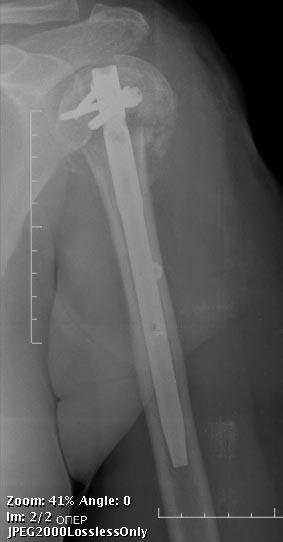

Любой вид остеосинтеза нужно "оставить" тем, кто знает и умеет его использовать. Когда чего-то не умеешь, легче всего выказать пренебрежительное отношение - мол, это можно оставить им, мы-то по-другому. НаучИтесь - понравится. Вот примерчик, операция закрыто через 2 мес. после травмы.

Действительно, Multiloc сегодня лучший. Но дело не в конкретной модификации PHN. Вся проблема в обсуждаемом случае в отличной перспективе закрытой репозиции, которую жаль упускать. Сделать хорошую репозицию руками и джойстиками трудно, а дистрактор правильный мало кто применяет.

Речь не о вообще любых, или всех, переломах в этой области, а о конкретном этом случае (и подобных) - хирургическая шейка, большой бугорок не смещен. Когда действительно нужна открытая репозиция - это совсем другая история, и нет, очевидно, большой разницы, чем в итоге зафиксировали, еще и эндопротез бывает нужен. А тут - несколько разрезиков по 1 см, операция 20-30 мин. И между "минимальным смещением" и "3-4 фрагментах и значительном смещении" помещается много чего, вот как раз типа этого случая и того, что я показал.